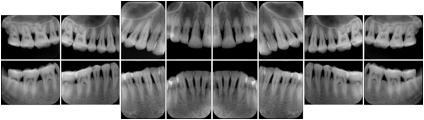

3. A dental provider wishes to capture a series of DICOM IO images for the patient’s dentition. The tooth morphology, teeth are divided into molars, premolars, canines and incisors, and a number of images for each jaw. The anatomic information was captured utilizing the triplet of schema. This standard code sequence is based on ISO 3950-2010, Dentistry - Designation system for teeth and areas of the oral cavity.

Every IO image should have anatomic information either through the primary or modifier sequence.

In most standard cases, images are oriented in structured layouts. These structured displays are useful to be shared between providers for reference purposes.

Table OO.1.1-1 shows structured display standard templates, where Viewset ID is based on the Japanese Society for Oral and Maxillofacial Radiology (JSOMR) classification provided by JIRA (Japan Medical Imaging and Radiological Systems Industries Association, www.jira-net.or.jp). Expected or typical teeth to be imaged location, region and designation codes are based on ISO 3950-2010, Dentistry - Designation system for teeth and areas of the oral cavity. For all the hanging protocols listed in OO.1.1-1, the value to use for Hanging Protocol Creator (0072,0008) is "JSOMR" and the value to use for Hanging Protocol Name (0072,0002) does not include "JSOMR" (e.g., "DL-S001A", not "JSOMR DL-S001A").